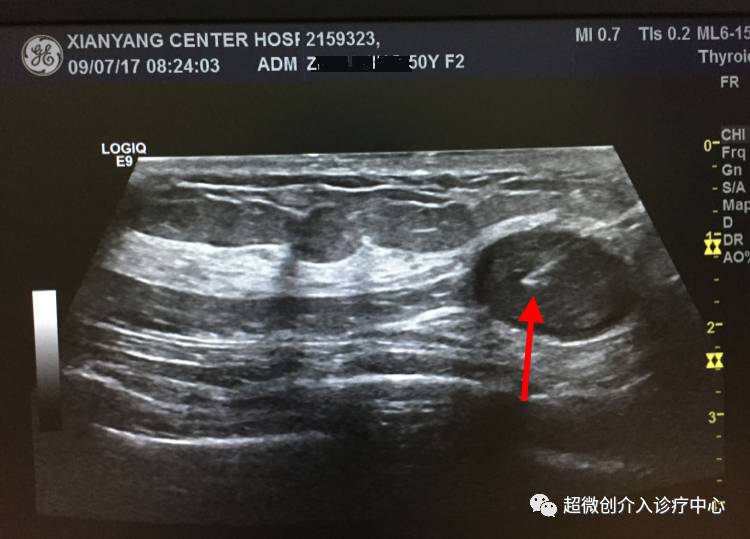

Case2 :

周*,F,50y,入住我院腺体血管外科。